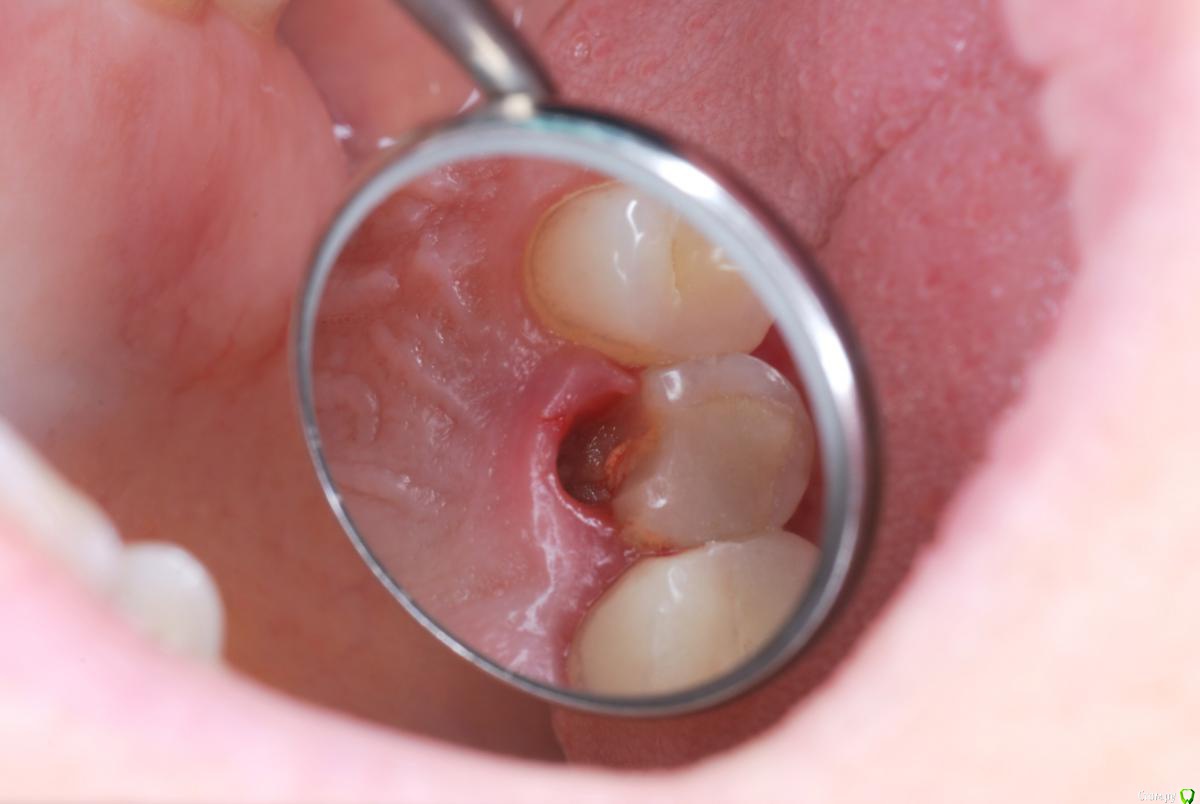

Сломался 15 верхний справа.

Сломанную часть удалили.

post-6232-0-07351300-1478030696_thumb.jpg

повозиться с десной значит придать такую форму десневого края что бы можно было восстановить зуб от границы скола в данном случае лишнее нужно будет убрать восстановить край и потом на верх керамическая накладка, найти врача в зависимости от того региона где вы проживаете, либо стучитесь в личку врачам на форуме либо воспользуйтесь темой для поиска врача с названием ищу врача в городе N

Хирургически снижая уровень десны вокруг причинного зуба для "правильной" постановки коронки запустится процесс снижения уровня десны вокруг рядом стоящих зубов. Потеря высоты десны - оголение корней - проблемы в ближайшем обозримом будущем.